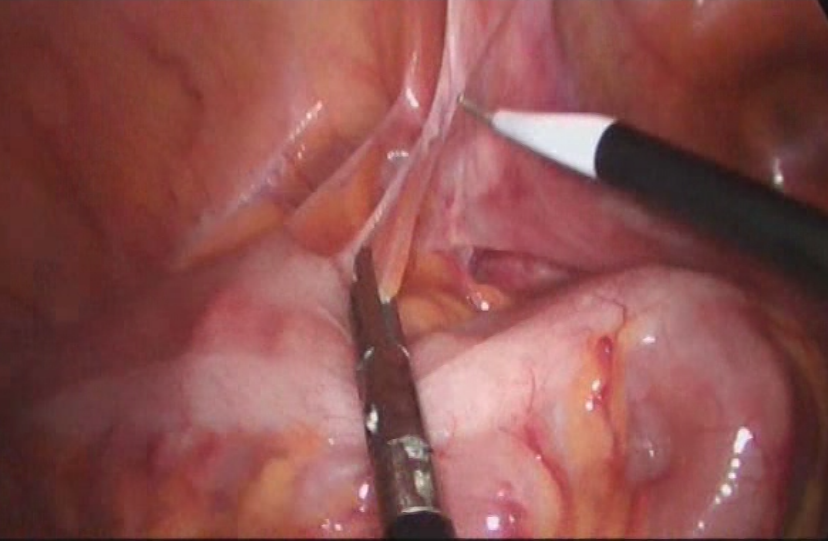

结直肠癌是我国常见的恶性肿瘤,患者就诊时多已为晚期或局部晚期。由于肿瘤瘤体巨大,侵犯邻近脏器,多个脏器受累,临床处理有一定困难。部分外科医生面对晚期结直肠癌时选择放弃手术。但事实上,多学科综合治疗能使晚期或局部晚期患者获得相对好的治疗结果,不应该轻易放弃合理的外科手术。对于肿瘤巨大但没有远处转移,有多脏器受累的患者,直接手术切除困难,可以考虑进行术前的辅助治疗。外科手术原则是在能够达到R0切除的基础上,尽量保留脏器的功能,进行合理的区域淋巴结清扫。

这老太太87岁,肠癌梗阻,病情较晚,在其他医院不敢做,准备放弃了,来我院经过处理后,微创手术解决问题。